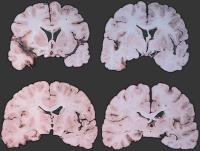

Temporallappenenzephalitis

Abbildung 5: Typischer - allerdings nur einseitiger - makroskopischer Aspekt einer Temporallappenenzephalitis durch HSV

Holoprosenzephalie

Abbildung 6: Holoprosenzephalie als Beispiel einer frühen Hirnschädigung ohne Noxenhinweis